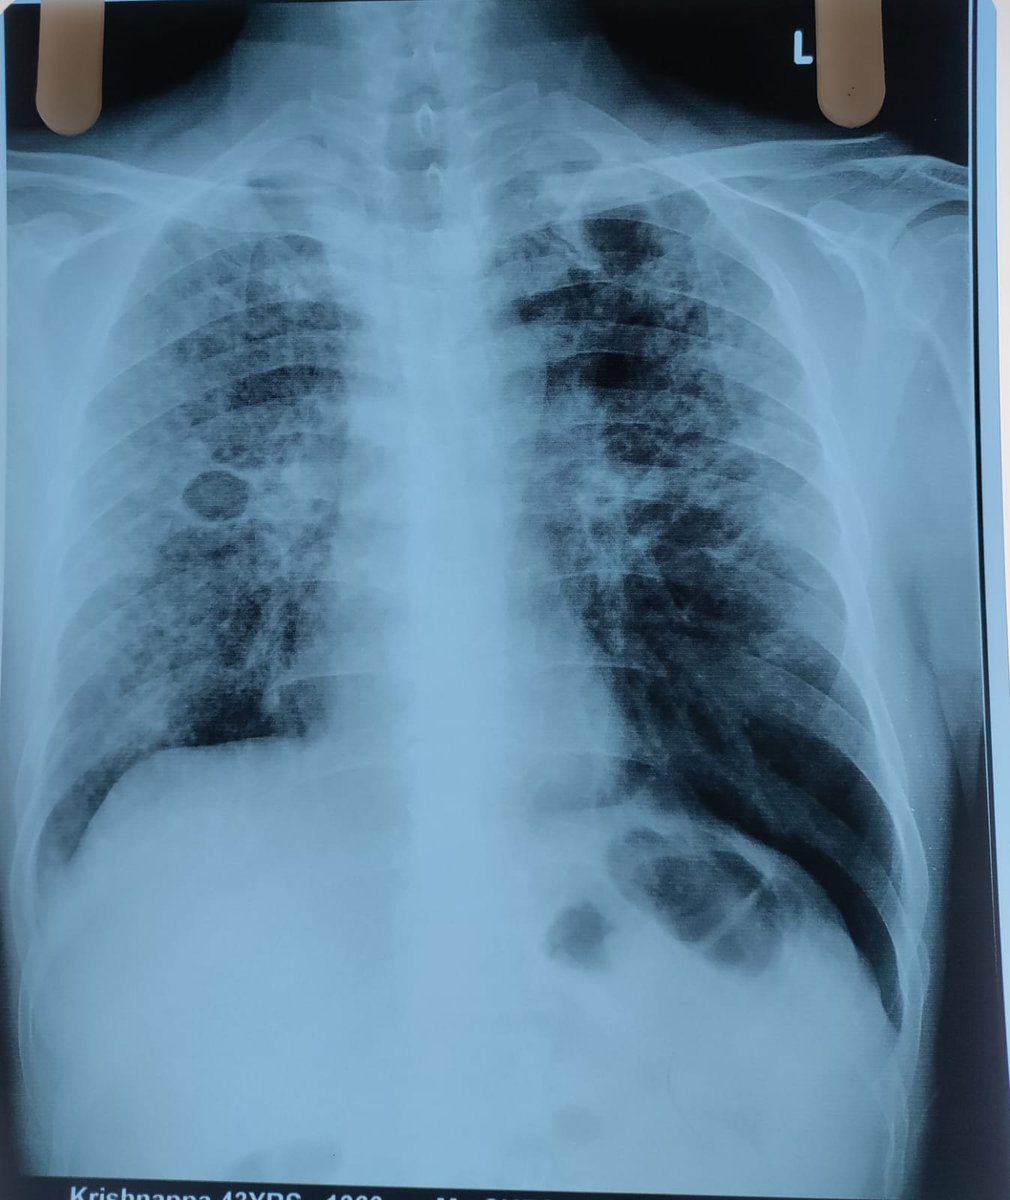

He walked into OPD with fever and cough… for one month.

He had been managing it, waiting, hoping it would settle.

Nothing dramatic at first glance.

But something didn’t feel right.

We moved quickly.

ESR was high.

Chest X-ray showed bilateral upper zone opacities… and a cavity in the right mid zone and left upper zone.

Now the story was clear.

Sputum sent for TrueNAAT.

Positive for TB.

All of this… within 120 minutes.

ATT started immediately.

Family advised screening.

Evaluated for other associated conditions.

One month of symptoms.

120 minutes to diagnosis.

TB doesn’t always shout.